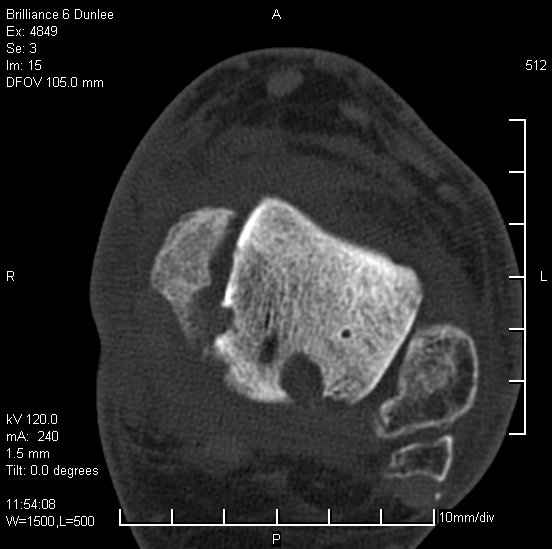

Асептический некроз таранной кости.

На лечении находится пациент 35 лет. Травма в сентябре 2008 г.- открытый вывих таранной кости

В день травмы ПХО, вправление вывиха, трансартикулярная фиксация. Рана зажила первично. С января нагрузка на конечность. С конца апреля- болевой синдром. На рентгенограммах и КТ признаки ас. некроза таранной кости, артроз подтаранного и голеностопного суставов.